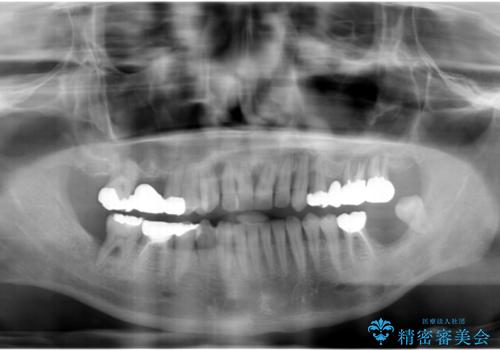

- 他院で上顎は全て抜歯し、入れ歯にする必要があると言われ相談に来院されました。

検査の結果、重度の歯周病であることから保存が難しい歯は抜歯を行いインプラントを、残すことが可能な歯には再生治療を含めた歯周病治療を行いより多くの歯を残す歯周病治療を計画します。

上顎は、残っている前歯も揺れがあり残すためにはクラウンでつなぐ歯周補綴が必要な状態です。

また咬合負担に不安のある前歯を助けるためにも、臼歯部にインプラント補綴を行いしっかりとかめる状態とすることも大切です。